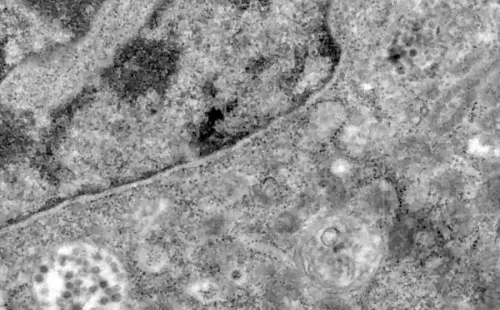

En la última imagen se registra a la célula con las partículas virales ya en su interior, totalmente infectada.

El Covid-19 ya infectó a las células (EFE).